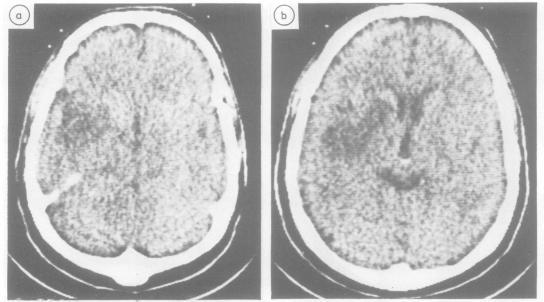

Limb apraxia was investigated with standardised tests in 14 patients whose CT scan provided evidence of a vascular lesion confined to the left basal ganglia, or the thalamus, or both, and not involving the cortex or adjacent white matter. Five patients were severely impaired in imitating movements and pantomiming object use. Four of them also performed poorly when tested with real objects. In two patients the lesion was primarily thalamic and in three the lesion was primarily in the lenticular nucleus and the posterior limb of the internal capsule. Patients without apraxia generally had smaller injuries, but there were exceptions. Apraxia is currently conceived of as due to damage of cortical areas and their cortico-cortical connections, but the present data suggest that the model should be enlarged to include the deep nuclei and the pathways running through them.

我们使用标准化测试对14例患者的肢体失用症进行了研究,这些患者的CT扫描显示血管病变局限于左侧基底神经节、丘脑或两者,且未累及皮质或相邻白质。5例患者在模仿动作和比划使用物体时严重受损。其中4例在使用真实物体进行测试时表现也很差。2例患者的病变主要在丘脑,3例患者的病变主要在豆状核和内囊后肢。没有失用症的患者损伤通常较小,但也有例外。目前认为失用症是由于皮质区域及其皮质 - 皮质连接受损所致,但目前的数据表明,该模型应扩大到包括深部核团及其之间的传导通路。